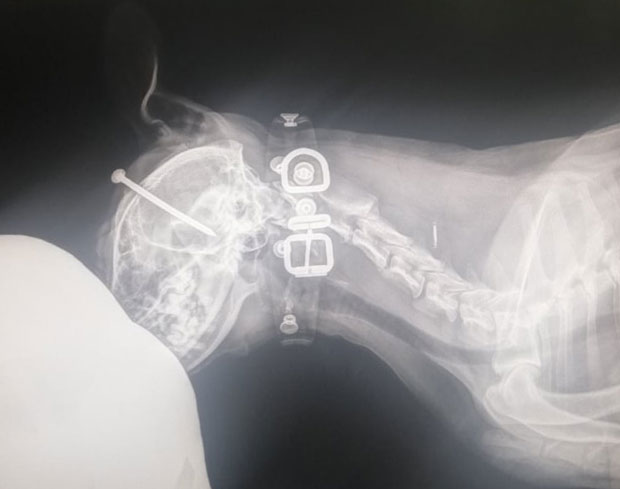

Zlostavljanje psa u Novom Sadu: DVANAESTOGODIŠNJI dečak ukucao EKSER životinji u LOBANJU!

NOVOSADSKA policija je danas pronašladvanaestogodišnjeg dečakaiz Novog Sada koji je psu zabio ekser u lobanju, saznaju “Novosti”.